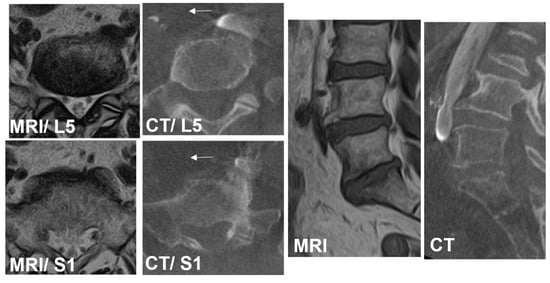

• Case 2: 76 years old, female, pseudarthrosis of L5/S1 transforaminal interbody fusion.

The preoperative CCW was 7.4 mm and 9.6 mm at the L5 and S1 levels, respectively. The lateral corridor approach was conducted instead of the OLIF51 approach (Arrows). The iliolumbar vein was ligated and interbody fusion was conducted successfully (Figure 7).

Figure 7. Case 2: 76 years old, female, pseudarthrosis of L5/S1 transforaminal interbody fusion. The preoperative CCW was 7.4 mm and 9.6 mm at the L5 and S1 levels, respectively. The lateral corridor approach was conducted instead of the OLIF51 approach (arrows) (A,B). The iliolumbar vein was ligated successfully (C).